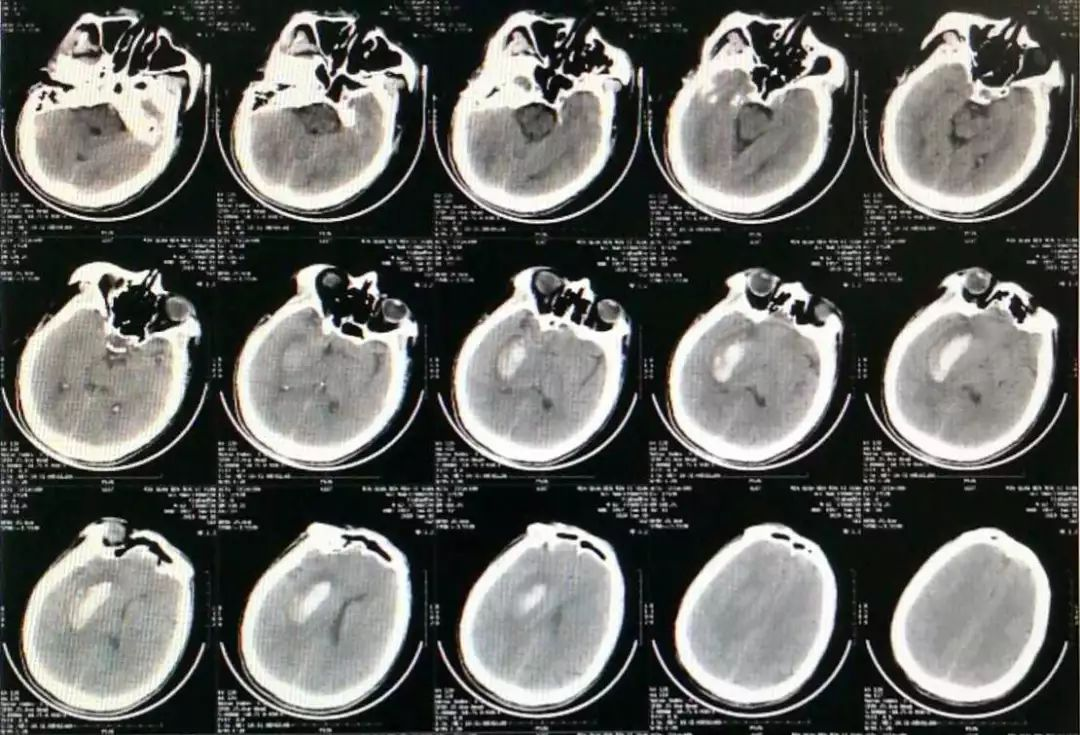

我们再来看另一例脑出血,也是可能与酒精、口服抗凝药物有关。

发病时CT:

第四天CT:

可见血肿呈分层现象,血肿周围水肿带明显,利用3D测量其各相关CT阈值。

利用3D技术模拟设计穿刺血肿,重建血肿体积约26ml

在3D打印导板下成功穿刺血肿,有约16ml暗褐色不凝血肿液引出,术后应用尿激酶一次,CT复查: